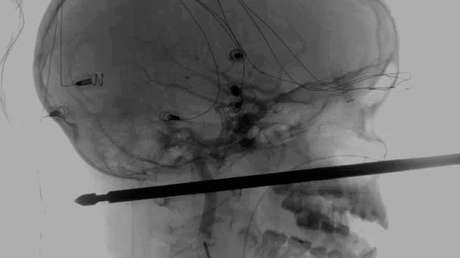

Xavier Cunningham, un niño de 10 años residente en Harrisonville (Misuri, EE.UU.) sufrió el pasado sábado un aparatoso accidente en el jardín de su casa. Se cayó de su casita del árbol y aterrizó sobre un pincho (chuzo o brocheta) para carne que le atravesó la cabeza. A pesar de introducirse por la mejilla y salir por la nuca, el menor ha sobrevivido y no tendrá secuelas.

El pincho de metal no le tocó los ojos, ni la médula espinal, ni ningún vaso sanguíneo. El periódico Kansas City Star, que recoge la noticia, dice que los médicos afirman que es un "milagro" que esté vivo después del percance sufrido.

Koji Ebersole, el director de Neurología Endovascular del sistema de salud de la Universidad de Kansas, relató el proceso para tratar al menor desde que llegó con el utensilio, que sobresalía medio metro de su cara, a través de un video publicado por la Universidad. Cuenta que su principal preocupación eran los vasos sanguíneos del cuello y que requerían de la colaboración activa del niño para poder llevar a cabo la operación.

Xavier demostró ser "extraordinariamente resistente y valiente" y aceptó esperar hasta el domingo, prosigue Ebersole. Después de sopesar varias opciones, el equipo médico pudo sacar con éxito el pincho y opinan que el menor podrá recuperarse por completo.